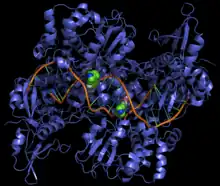

Chez les bactéries, le ou les chromosomes sont souvent circulaires et se trouvent dans un état topologique particulier caractérisé par un surenroulement négatif. Ce surenroulement négatif est essentiel à la réplication de l'ADN [et aussi à sa transcription en ARN messager (alias ARNm)] et constitue une caractéristique de l'ADN bactérien. C'est l'ADN gyrase qui introduit ce surenroulement négatif dans l'ADN. Cette enzyme, de la famille des topoisomérases est essentielle à la survie des bactéries, mais n'a pas d'équivalent chez les eucaryotes. Il existe des antibiotiques qui bloquent l'action de l'ADN gyrase, il s'agit des aminocoumarines et des quinolones[8]. Plus récemment, ces dernières ont été supplantées par les fluoroquinolones, molécules de synthèse permettant de contourner les mécanismes de résistance aux quinolones.

Mutation de la cible de l'antibiotique

Chaque antibiotique agit en se fixant sur une cible précise dans la cellule : paroi, ribosome... La présence d'une modification consécutive à une mutation modifie le site de fixation et empêche ainsi la liaison de l'antibiotique. C'est un des mécanismes de résistance à la streptomycine, l'un des premiers antibiotiques utilisés pour traiter la tuberculose. C'est aussi l'un des principaux mécanisme de résistance à la rifampicine qui est l'un des antibiotiques qui a remplacé la streptomycine. On observe des mutations de l'ARN polymérase bactérienne qui bloquent la liaison de la rifampicine. Les acides aminés mutés sont situés à proximité immédiate du site de fixation (voir figure à droite).